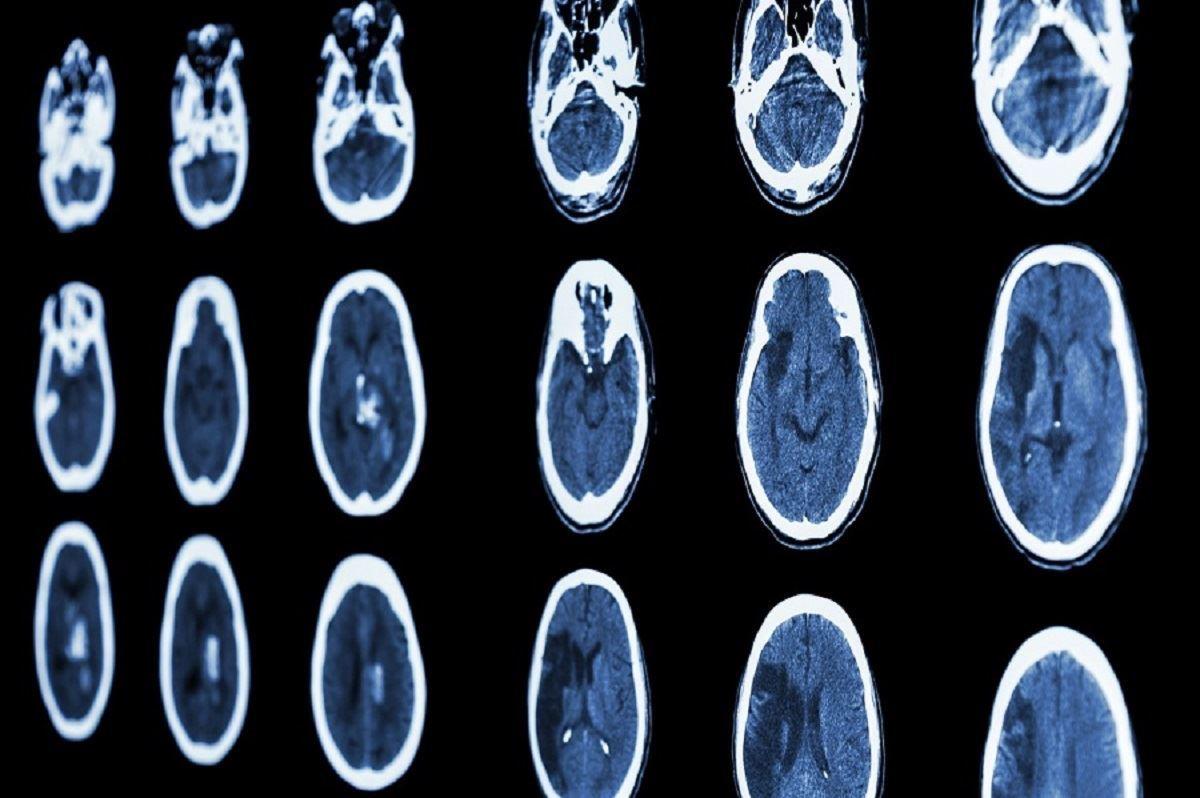

ابتلا به کرونای حاد مغز را 20 سال پیر می‌کند

محققان دانشگاه کمبریج می‌گویند ابتلا به کرونای حاد می‌‌تواند روی توانایی‌های شناختی و مغز افراد تاثیرگذار باشد تا جایی که اثر این بیماری معادل بیست سال پیر شدن مغز است.

به گزارش رادیونشاط، در یک مطالعه جدید، محققان 46 بیمار مبتلا به کرونای حاد را با 460 شخص همسان – از نظر ویژگی جسمی و سنی – مقایسه کردند. آن‌ها دریافتند تاثیر ویروس کرونا بر بدن شش ماه پس از ابتلا معادل با پیری 20 ساله یا از دست دادن 10 امتیاز هوشی است.

نتایج نشان داد کسانی که از ویروس کرونا جان سالم به در برده‌اند، دقت کمتری داشتند و زمان پاسخ‌دهی آن‌ها نسبت به عموم مردم طولانی‌تر بود. این حالت مشابه با پیر شدن به اندازه 20 سال – بروز اثرات پیری بین 50 تا 70 سالگی –  و یا از دست دادن 10 امتیاز IQ بود.